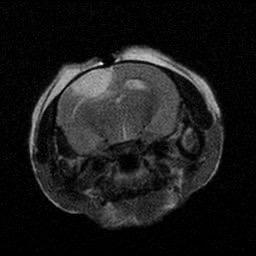

Figure 2. (A-B) Representative MRI images showcasing the lesioned brain area ofChrdl1 Ckoand Cre(-)mice at1daypost-stroke and 7days post-stroke. (C) Bar graph comparison of stroke volume between Cre (-) andCkomice,1dayand7dayspoststroke.Statisticaldifferencesbetween groups or time points, where applicable, are indicated by asterisks (*p< 0.05, **p<0.01). (D) Line graph comparison of stroke area percentage betweenCre(-)andCkomice,1dayand7dayspoststroke.